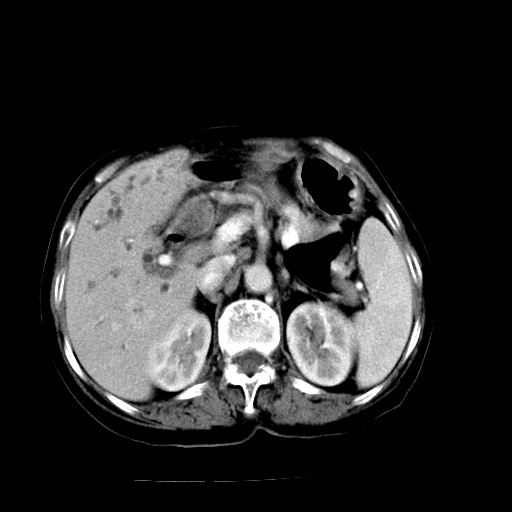

以下是引用卜一在2009-4-7 5:06:00的发言:[br]左右肝内胆管结石伴扩张合并胆系感染;不除外胆管细胞癌可能。支持! [br] [br]

以下是引用随光逐影在2009-4-7 8:21:00的发言:[br]肝内外胆管多发性结石并肝内外胆管扩张;胆系感染。